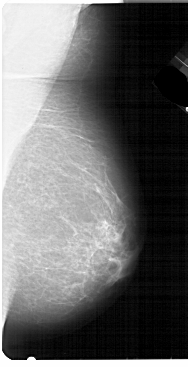

A_1948_1.RIGHT_CC

RIGHT_MLO LINES 5491 PIXELS_PER_LINE 2806 BITS_PER_PIXEL 12 RESOLUTION 43.5 NON_OVERLAY